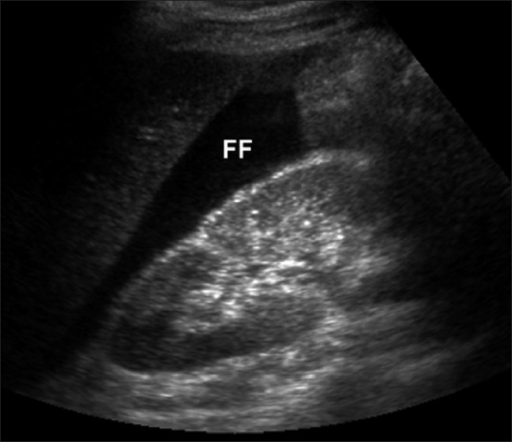

RUQ

This view is the easiest as the liver is a large acoustic window. Abdominal free fluid often collects here first, or in the pelvis. Ensure the tip of the liver is visualised as free fluid there is often missed if the collection is small.

Jyothi PSLS, Kalra VB - CC BY-NC-ND 4.0, Link